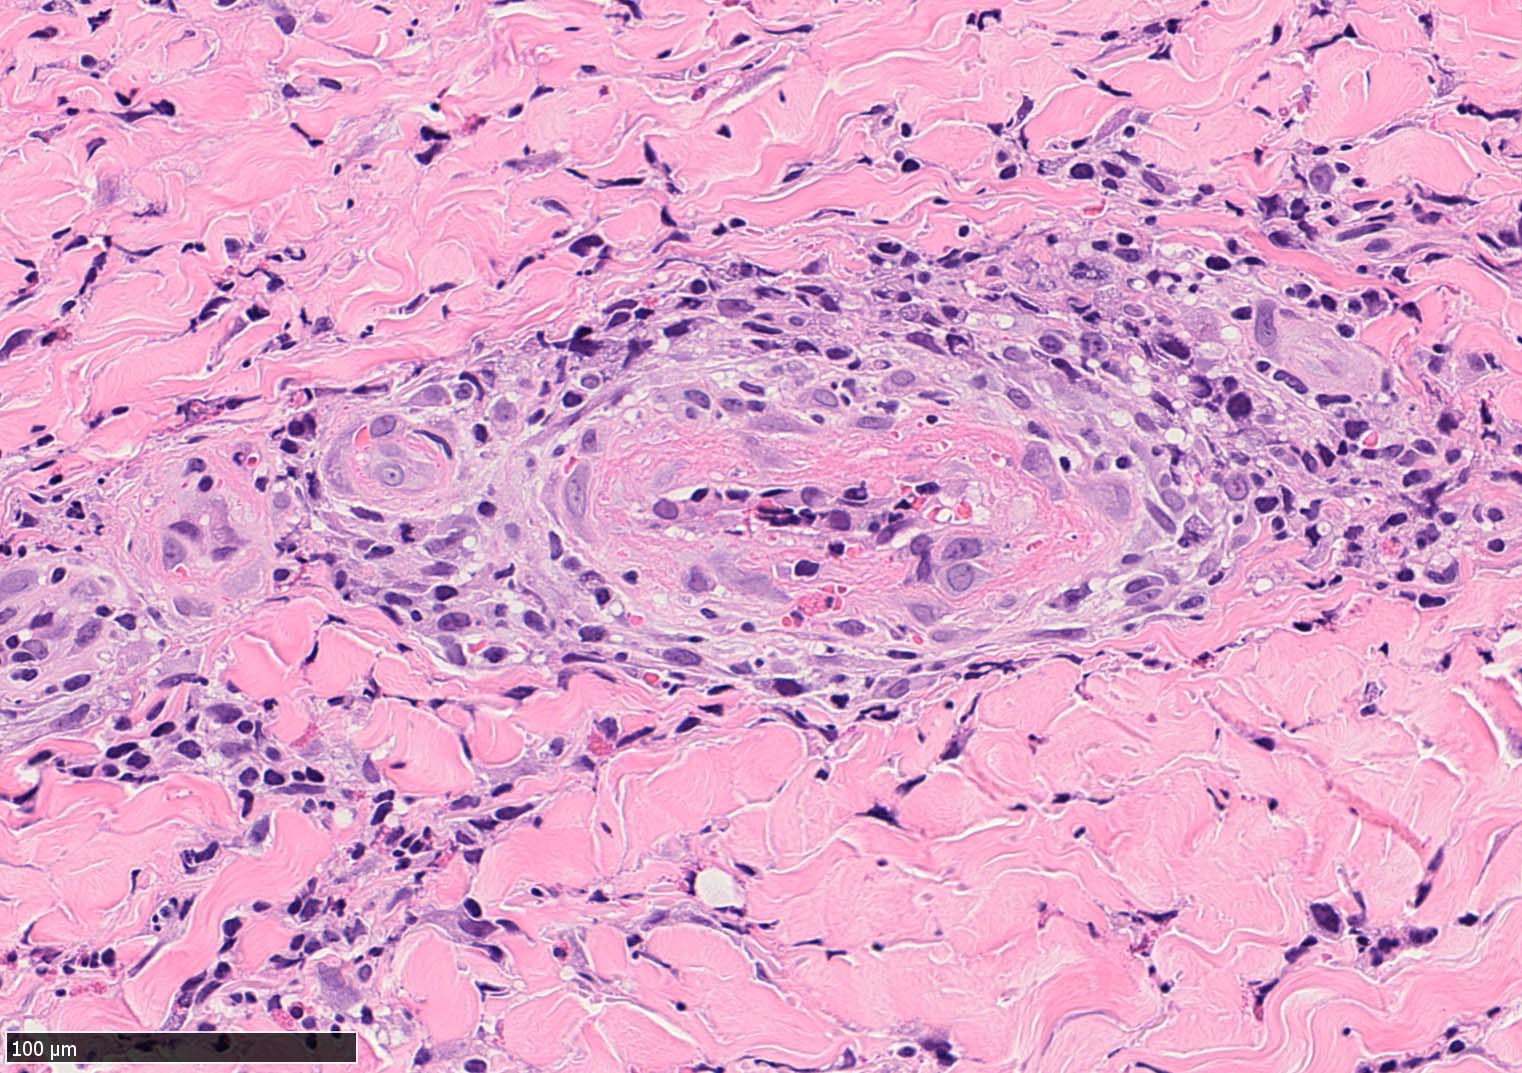

痂皮の下に硝子様凝固物があり, 周囲には壊死組織が形成されている. 近傍の細血管には凝固物による閉塞の所見があるように見える. 連続する細血管には, fibrinoid necrosisを呈する壊死性血管炎が認められる.